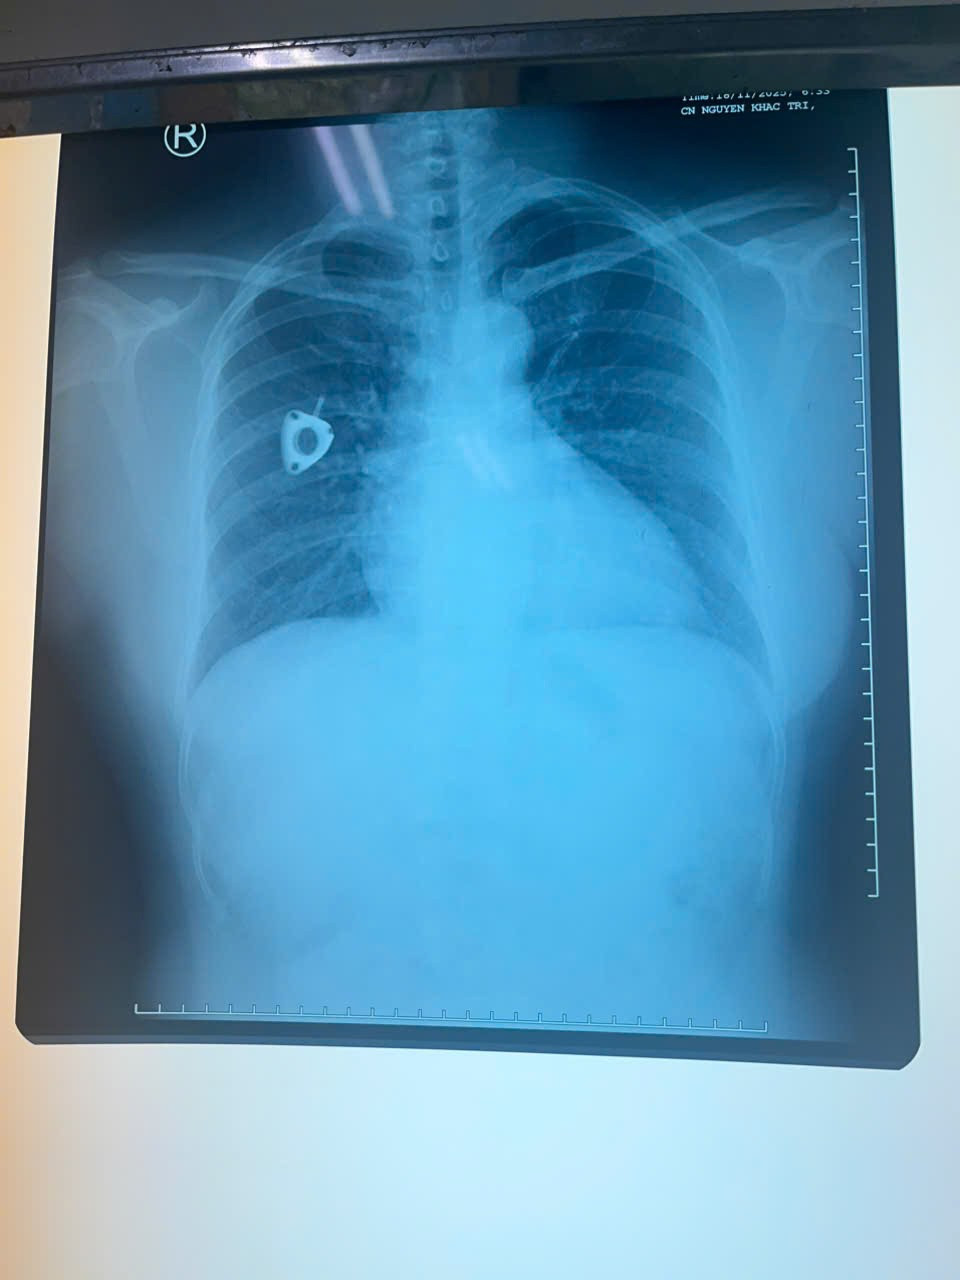

Hình ảnh X quang cho thấy dị vật ở động mạch phổi 2 bên.

Trong lần đi khám tầm soát tại một cơ sở y tế tư nhân, chị được chỉ định chụp CT ngực có tiêm thuốc cản quang, bác sĩ phát hiện hình ảnh một dị vật trong tim, nằm vắt ngang tại vị trí động mạch phổi hai bên.

Sau khi được tư vấn về khả năng cần thực hiện thủ thuật can thiệp lấy dị vật, bệnh nhân quay về bệnh viện đã điều trị ung thư trực tràng để tiếp tục thăm khám và được chụp Xquang ngực.

Bác sĩ ghi nhận catheter đã bị đứt, một phần còn tại vị trí dưới xương đòn phải, phần đầu ống truyền còn lại đã di chuyển về tim và nằm trong động mạch phổi. Bệnh nhân được chỉ định rạch lấy phần catheter còn lại dưới da, lấy phần catheter ra ngoài và được tư vấn đến Bệnh viện Quân y 175 để xử trí chuyên sâu phần trong tim.